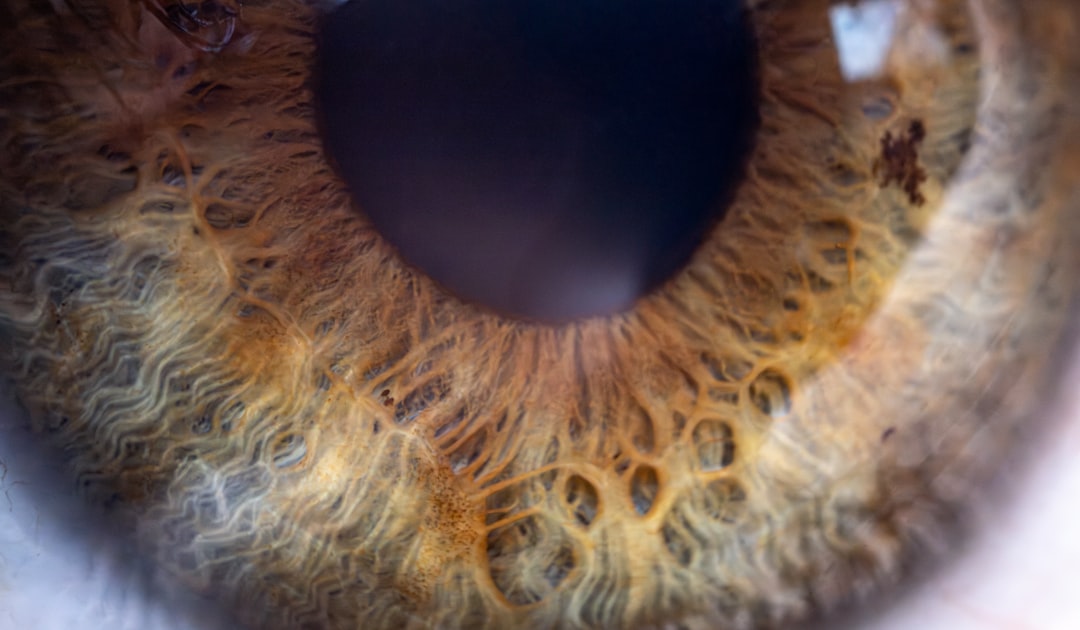

백내장 수술은 눈의 시력을 회복하기 위한 중요한 절차입니다. 하지만 수술 후 시력은 당장 좋아지지 않을 수 있으며, 여러 요인에 따라 시력 회복 기간이 달라질 수 있습니다. 일반적으로 많은 사람들이 수술 후 1~2주 이내에 시력이 서서히 회복되기 시작하지만, 완전한 회복에는 몇 주에서 몇 달이 걸릴 수 있습니다. 이 기간 동안 주의 깊게 관찰하는 것이 필요합니다.